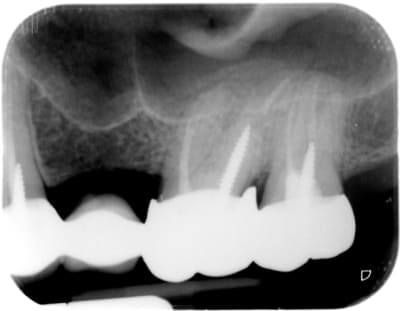

ce patient se plaint de saignements abondants et de douleurs

vives au passage des brossettes.

surcontour ne respectant pas l'espace biologique avec apparition future d'une poche parodontale mettant en péril l'avenir de la prothèse

second canal MV oublié sur la 7? téléphones au confrère conseille lui un cône beam

les surcontours on en voit plein mais pas de douleur au passage de la brossette

la nomenclature de merde qu'on a, fait qu'on oublie beaucoup de second MV, alors ne lui jeton pas la pierre

ou bien le canal distal de la 27?

Ici le debordement est evident et il y a une atteinte osseuse visible, le boulo est a refaire